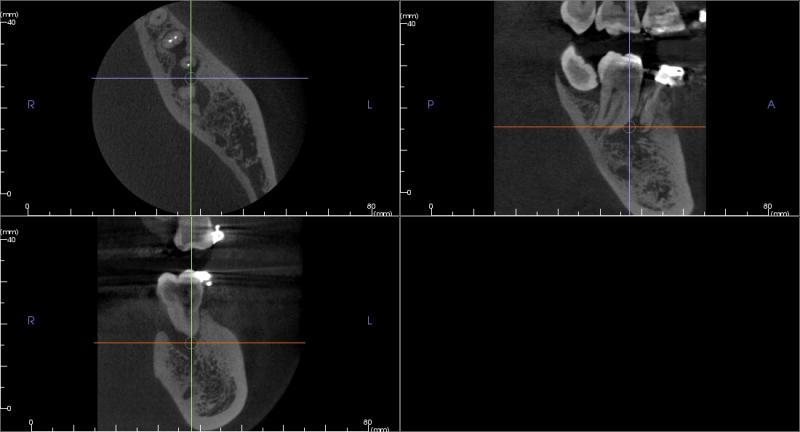

Example 2: RCT (root canal therapy)

Fig. 7 Cross-sectional views (slices), showing the extent of bone destruction: upper left = axial view, upper right = sagital view, lower left = coronal view